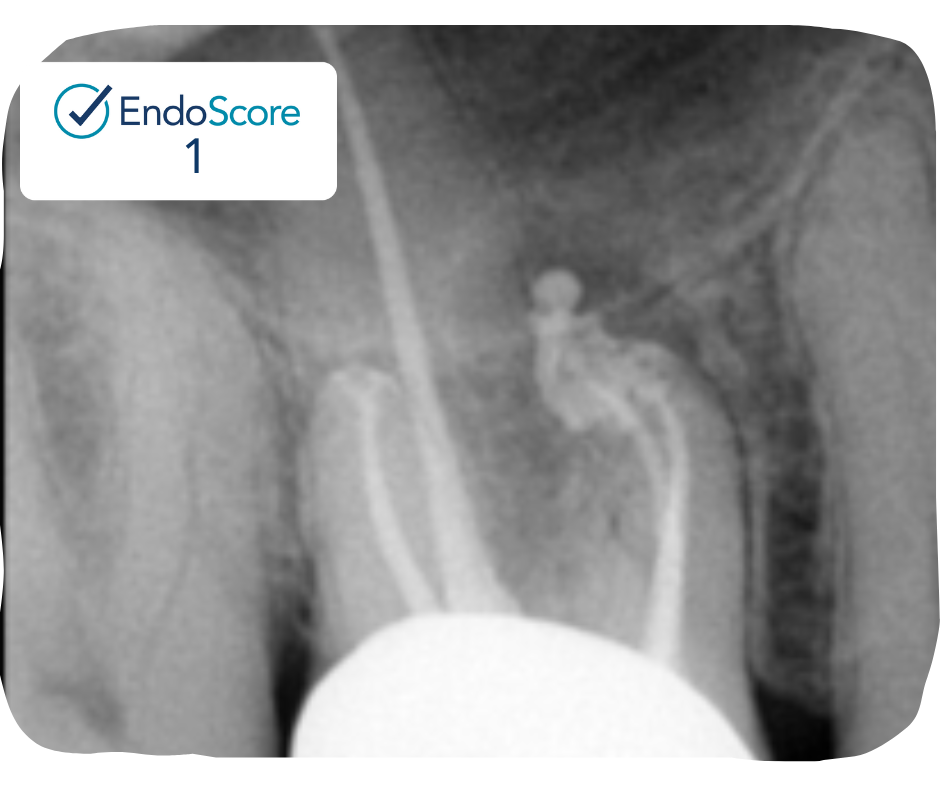

Case Study by Dr. Justin Kolnick

Endoscore of 69 was reduced to a final score of Endoscore 1 after MB2 canal was located and treated.

Obturated with EndoCeramicâ„¢ Sealer (Endo Direct) and single cone gutta percha.

EndoScore: 69 to 1